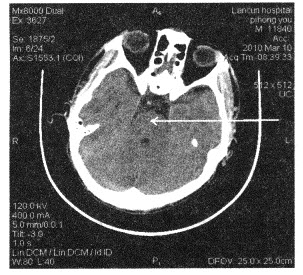

下面颅脑断层图像中箭头所指为()

A:延髓

B:脑桥

C:中脑

D:小脑

E:小脑蚓部